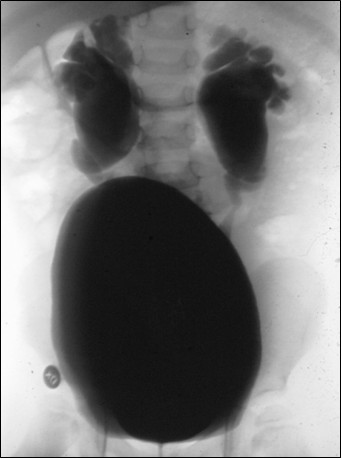

Dziewczynka 3-miesięczna została przywieziona do Izby Przyjęć z powodu wysokiej gorączki. W badaniu przedmiotowym zwracał uwagę twór wystający poza wargi sromowe (patrz obrazek). Jakie rozpoznanie jest najbardziej prawdopodobne?